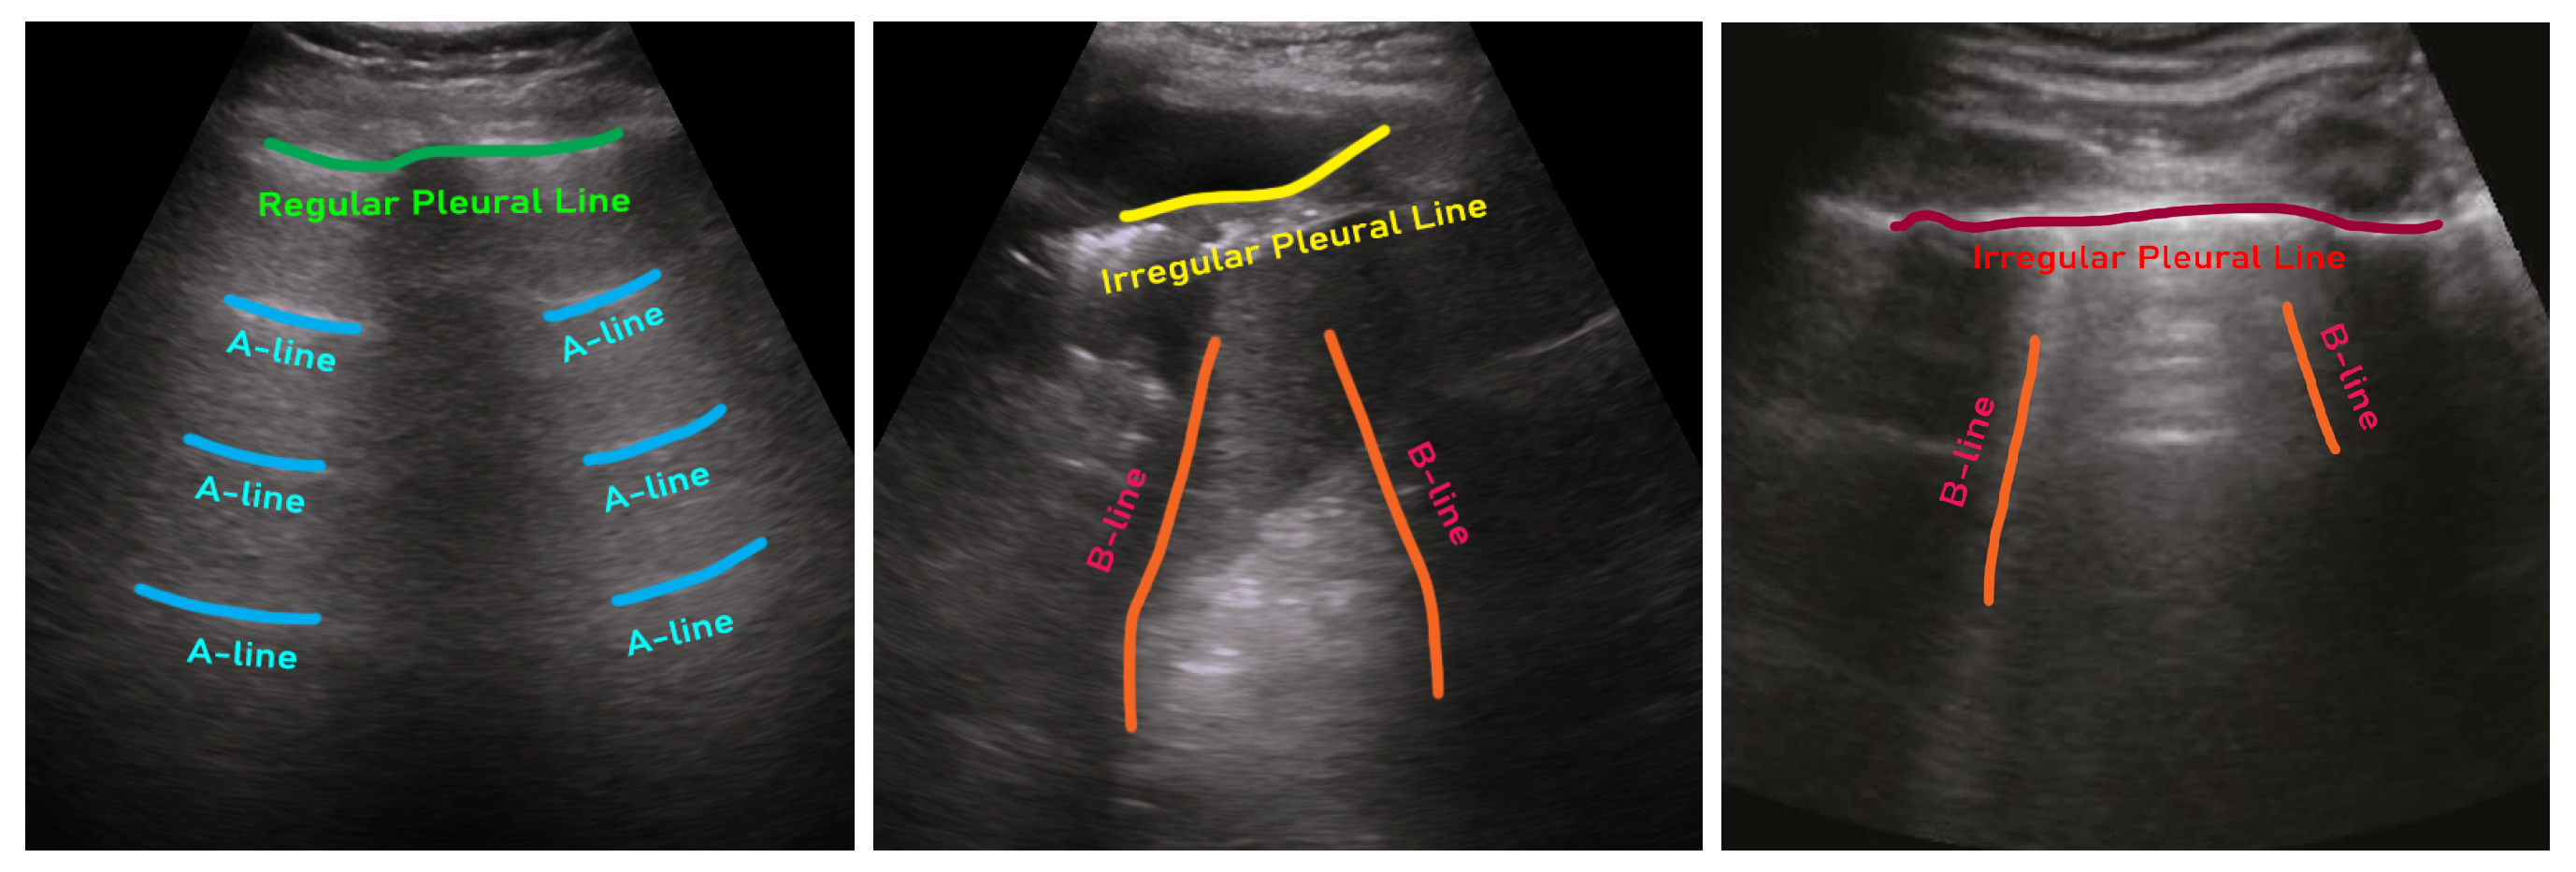

Typically, three major tasks can be performed on LUS images for COVID-19 patient management: (i) detection of pneumonia infection in the lung (e.g., [13,15,24,33]), (ii) pneumonia type/severity classification (e.g., [18,20,23,32,81]), and (iii) segmentation of infection in the lung (e.g., [98]). There are usually three types of artifacts that can appear in a LUS image, such as A-lines, B-lines, and irregular pleural lines (see Figure 1) [85]. When ultrasound pulses reach the surface of the lung, healthy lungs exhibit horizontal lines parallel to the surface of the transducer, known as A-lines. On the other hand, a lung infected with pneumonia shows irregular pleural lines, as well as brightness in the lung (see Figure 2). On the contrary, COVID-19, a special kind of pneumonia, typically shows discreet vertical reverberation artifacts, known as B lines, which originate from the pleural surface (see Figure 1 and Figure 2) [23,32]. Based on the presence and appearance of these artifacts, pneumonia can be detected and classified as community-acquired pneumonia (CAP) and COVID-19, respectively. Finally, using segmentation, the spread of pneumonia can be estimated, which can be used for the severity scoring criteria for COVID-19 [19,86].